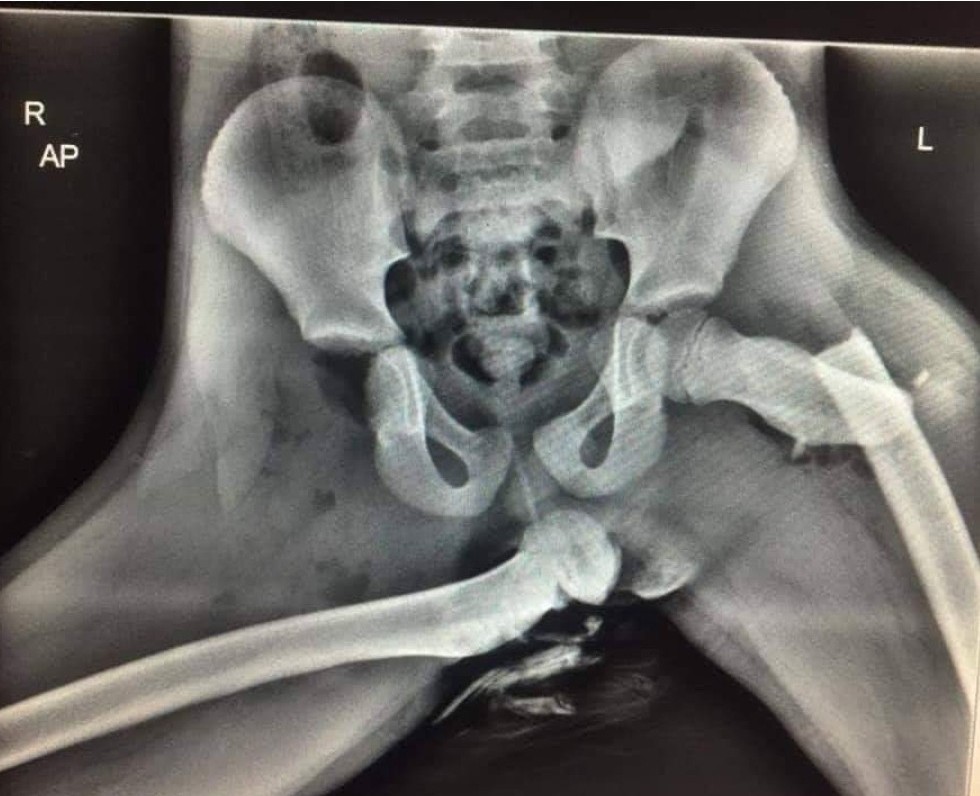

The below image is from a non fatal 30mph collision, this is the passenger who has their feet up on the dash.

#feetinthefootwellpic.twitter.com/zuQiOn7v3C